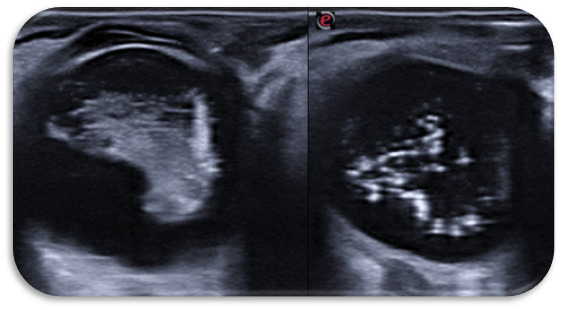

El segundo caso: cristalino con cápsula engrosada y punteado blanquecino compatible con cataratas, en cuerpo vítreo posterior: imagen de punteado compatible con hialosis asteroidea. Retina plegada.

FO Caso 2: Difícil visualización por hialosis asteroidea + opacidad de medios, retina aparentemente aplicada.